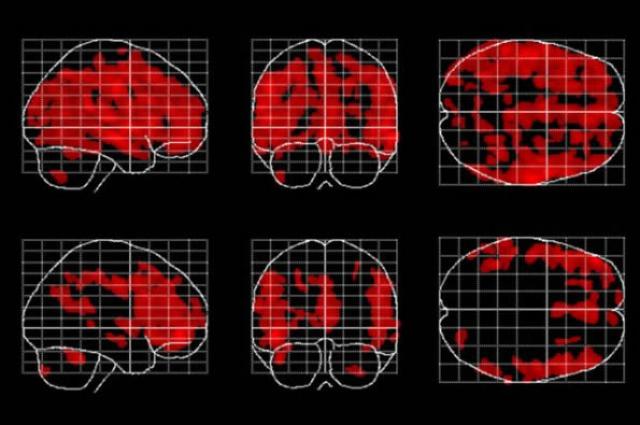

Com o avanço da tecnologia de imagem cerebral, novos estudos foram feitos comprovando que os efeitos da meditação vão muito além do que pôde ser percebido inicialmente. O aumento da substância cinzenta no córtex frontal em áreas relacionadas à memória e tomada de decisões é especialmente importante pois é amplamente documentado o fato de que o córtex diminui de tamanho com o envelhecimento do indivíduo -

Áreas do cérebro afetadas pelo envelhecimento (em vermelho) estão presentes em menor quantidade e são menos espalhadas em pessoas que meditam (linha inferior) que em pessoas que não meditam. Cortesia: Dr. Eileen Luders / UCLA